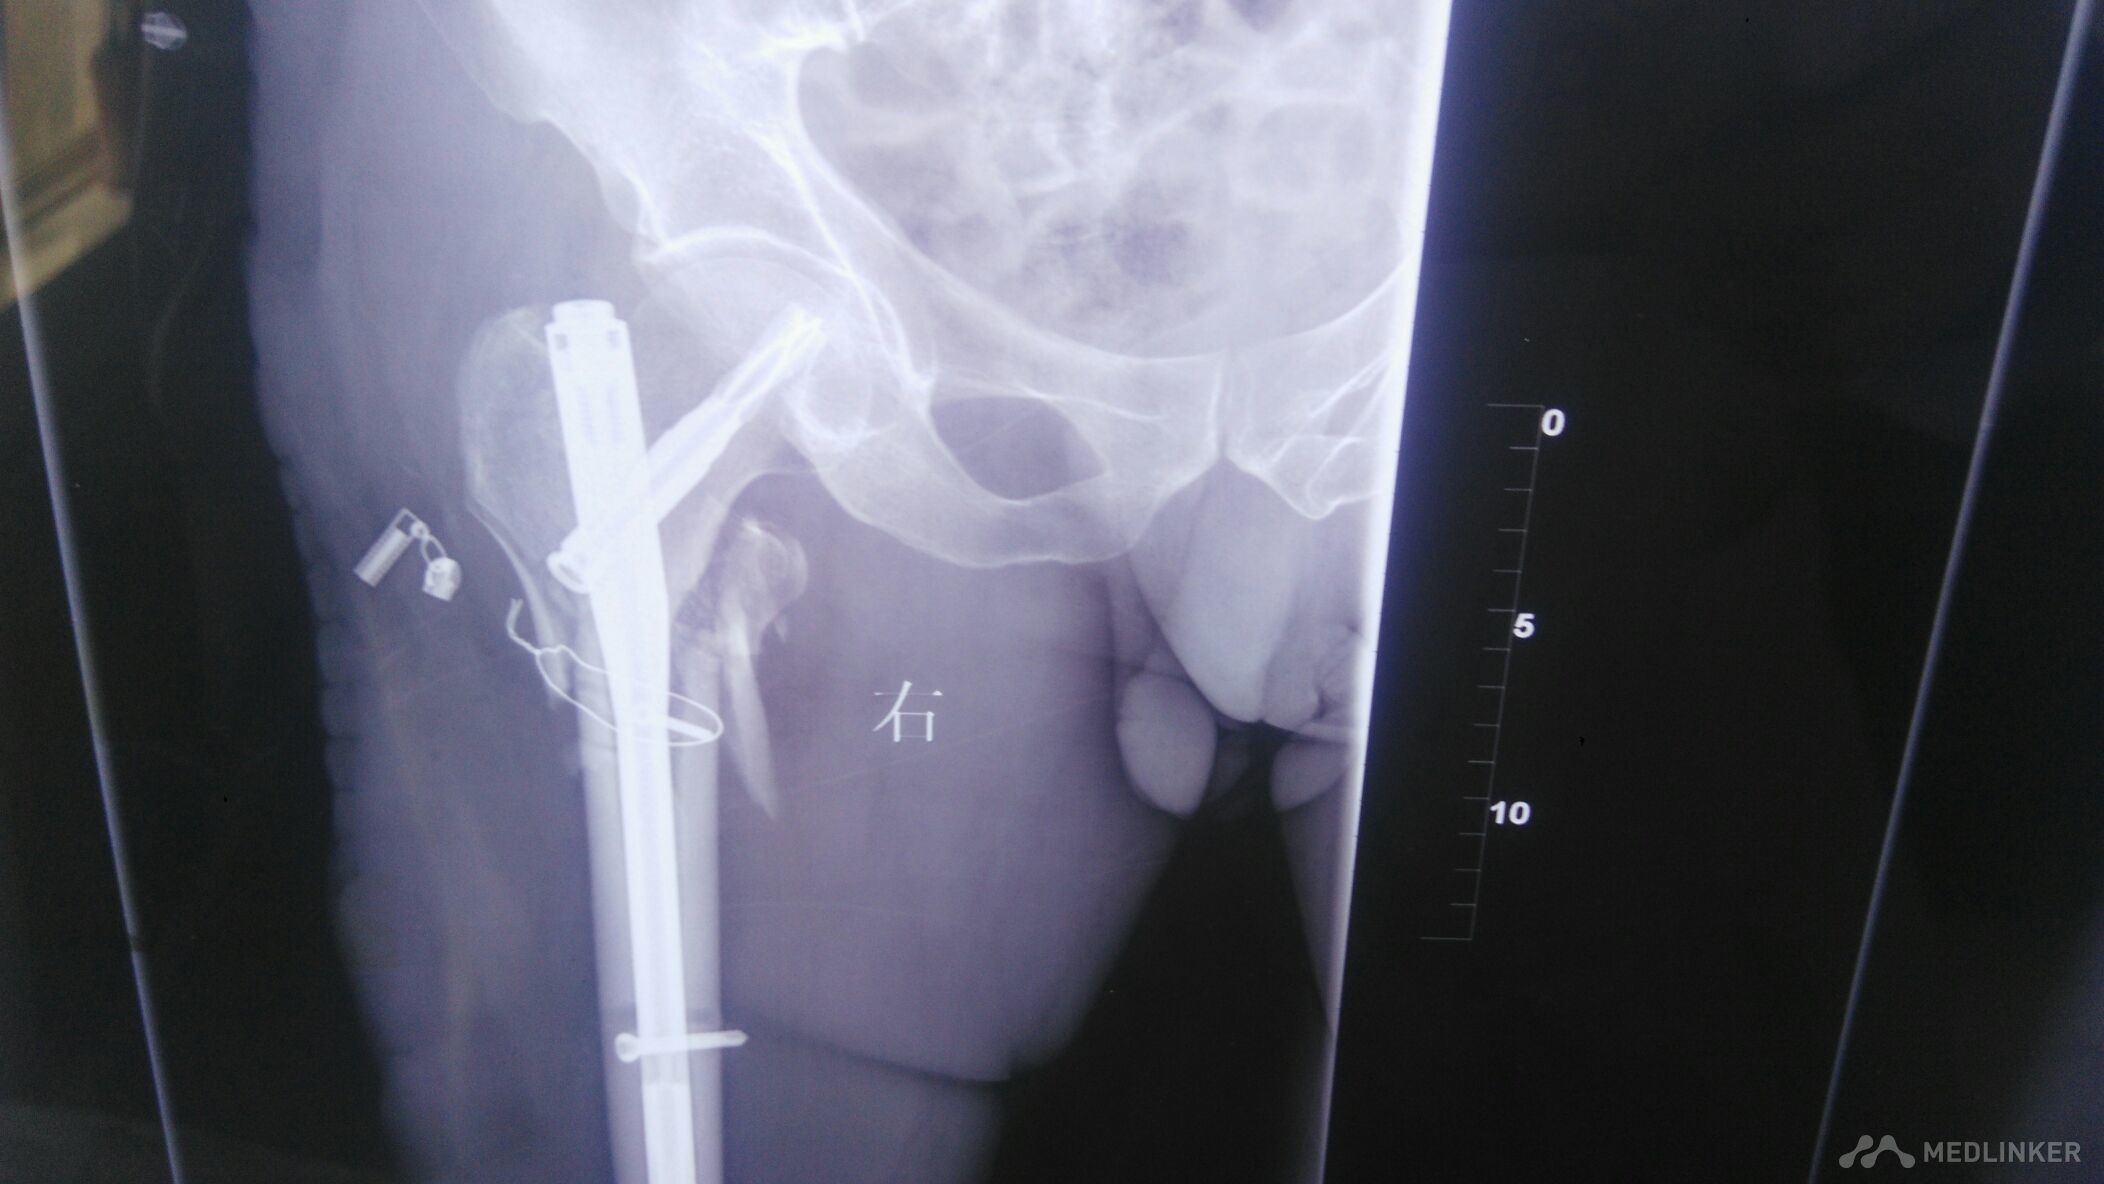

髋部手术。髋部畸形明显,肿胀明显。以股骨外侧为著。足部血运正常,感觉正常。

髋部手术,髋部肿痛,肿胀明显。压痛阳性,叩痛阳性。髋部活动受限。

沉痛的教训,下面的锁定,没有锁住,只能相当于阻挡钉。逼住主钉。髋部力线改变。防旋能力差。